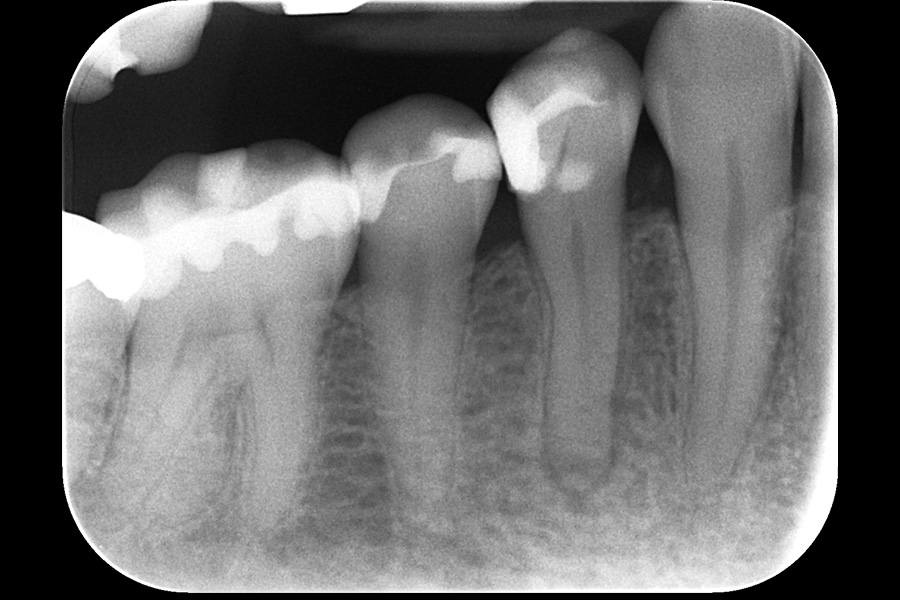

治療後